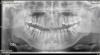

Ferny Опубликовано 11 мая, 2011 Поделиться Опубликовано 11 мая, 2011 Уважаемые коллеги! интересует зуб 11 к сожалению прицельных рентгенов нет Пациент жаловался на неприятные ощущения в области 11 зуба. Перкуссия болезненная, на десне был свищ...открыла канал, пульпа экстирпирована, в канал положен кальций. Осталось самое главное почистить и обтурировать. до скольки лучше расширять инцисив? а также вопрос по поводу зуба 45...здесь надо ретрит делать? и на сколько лучше расширять..на пару размеров или на 1 размер больше? если например бует ширина 30 то расширить до 40 или лучше до 35? и ещё что лучше использовать при перелечивании...хлорку или хлоргексидин? зуб 37 и 47 тоже нужно бы перелечить....и если передечивать то только те каналы под которым воспаление? извиняюсь за такие может быть глупые вопросы, но я пока ещё только учусь) спасибо за внимание=) Ссылка на комментарий